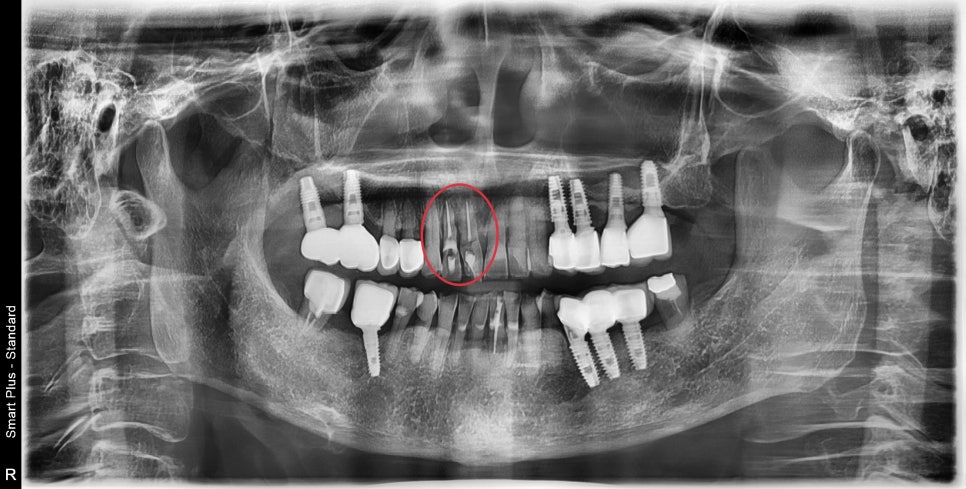

해당 부위의 엑스레이입니다

과거에 신경치료가 되어있는 상태였으며

해당 치아는 치주염이 생겨있고 동요도도 관찰이 되었습니다.

좋지 않은 치열은 치아 주변의 잇몸의 형태 변화, 염증의 발생의 원인이됩니다.

이미 많이 흔들리는 치아들은 발치가 필요해 보였으며

임플란트 후 주변 치아들과 잇몸에 대한 평가가 필요했습니다.